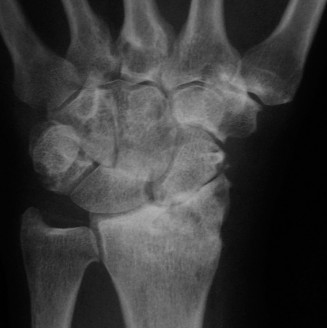

Identify the cause of implant loosening in wrist fusion? CASE 19 ### Several months after sustaining a fall on his outstretched hand, a patient presents to your clinic with pain over the central part of his wrist. You obtain the following x-ray (Fig. 3–16). What do you see?

Figure 3–16(©) Sunil Thirkannad and Christine M. Kleinert.

The correct answer is (D).